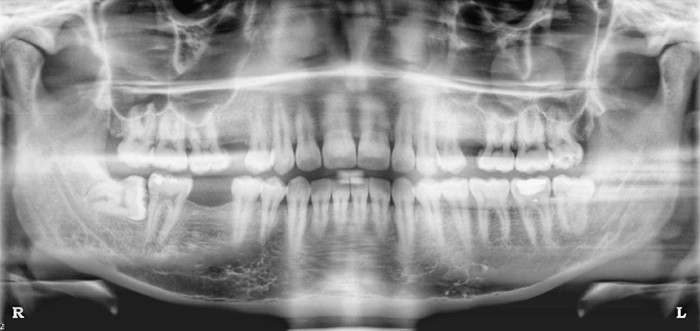

2 / 25

2. (Select ONE OR MORE correct answers)

The radiograph shows evidence of